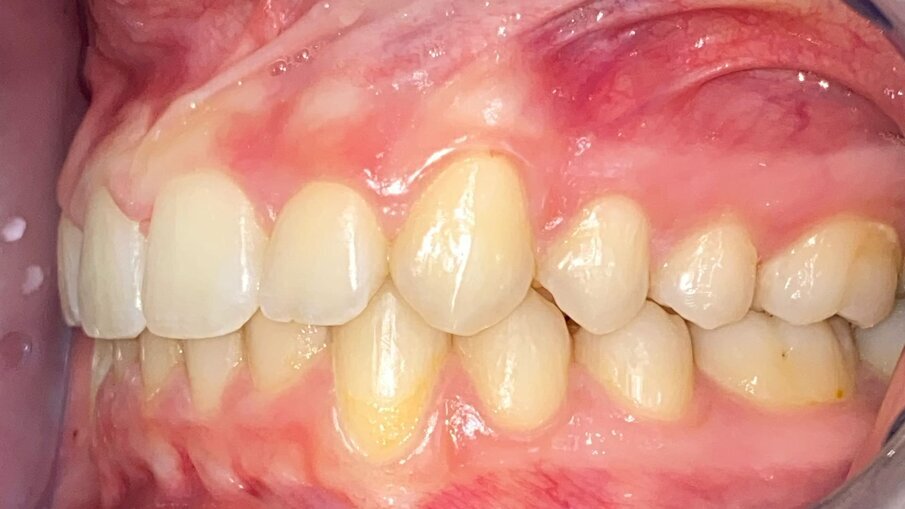

All’esame obiettivo intraorale si riscontra sul piano frontale un severo morso profondo con precontatto traumatico degli incisivi superiori contro la papilla retroincisiva e le rughe palatine anteriori durante la massima intercuspidazione, con overbite di 10 mm (Fig. 5). Dalle foto laterali si evidenzia una malocclusione di Classe II divisione 2 con scissor bite dell’elemento 1.5 (Figg. 6, 7), mentre dalle foto occlusali si rileva un grave affollamento con contrazione di entrambe le arcate maggiore nella zona premolare (Figg. 8, 9). L’analisi di Bolton mostra un eccesso superiore 3-3 di 2,34 mm (73,6%) e 6-6 di 2,76 mm (88,8%). L’analisi cefalometrica evidenzia una Classe II scheletrica, modello facciale normodivergente, angolo interincisale aumentato, incisivi superiori e inferiori retroinclinati (Fig. 10). La radiografia panoramica mostra la presenza dei germi dei terzi molari, assenza di parallelismo tra le radici dei premolari inferiori (Fig. 11) e una sovraeruzione degli incisivi inferiori che crea un doppio piano tra gli incisivi e i molari, segno di una curva di Spee molto profonda.

Fig. 7_Laterale sinistra pre-trattamento.